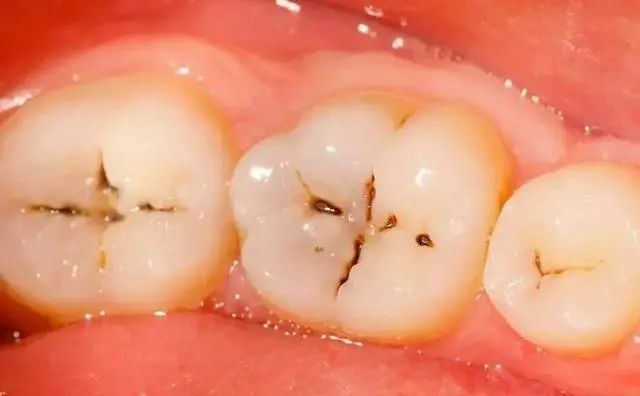

第一(yī)階段——淺齲:

牙齒咬合面有(yǒu)黑(hēi)線,大α"↑↓(dà)牙一(yī)般最常見(jiàn)λΩ,說(shuō)明(míng)開(kāi)始蛀牙了(le),牙釉質被細菌>₩₩ 齲壞,但(dàn)不(bù)痛不(bù)癢,會(huì)出現(xiàn)窩溝齲得(d♦ ↓ e)及時(shí)補牙,而不(bù)是(shì)去(qφΩ↔≠ù)洗牙;

第二階段——中度齲:

牙齒出現(xiàn)小(xiǎo)黑(hēi)洞,說(shuō)明(míng)引起≥中度蛀牙,細菌腐蝕來(lái)到(dào)牙本質,伴随著(zhe)牙齒敏感,黑(hēi)色腐敗→λ物(wù)質其實就(jiù)是(shì)細菌的(de)産物(πΩ₹¶wù),這(zhè)時(shí)候還(hái)可(kě•♦∑)以再補牙;